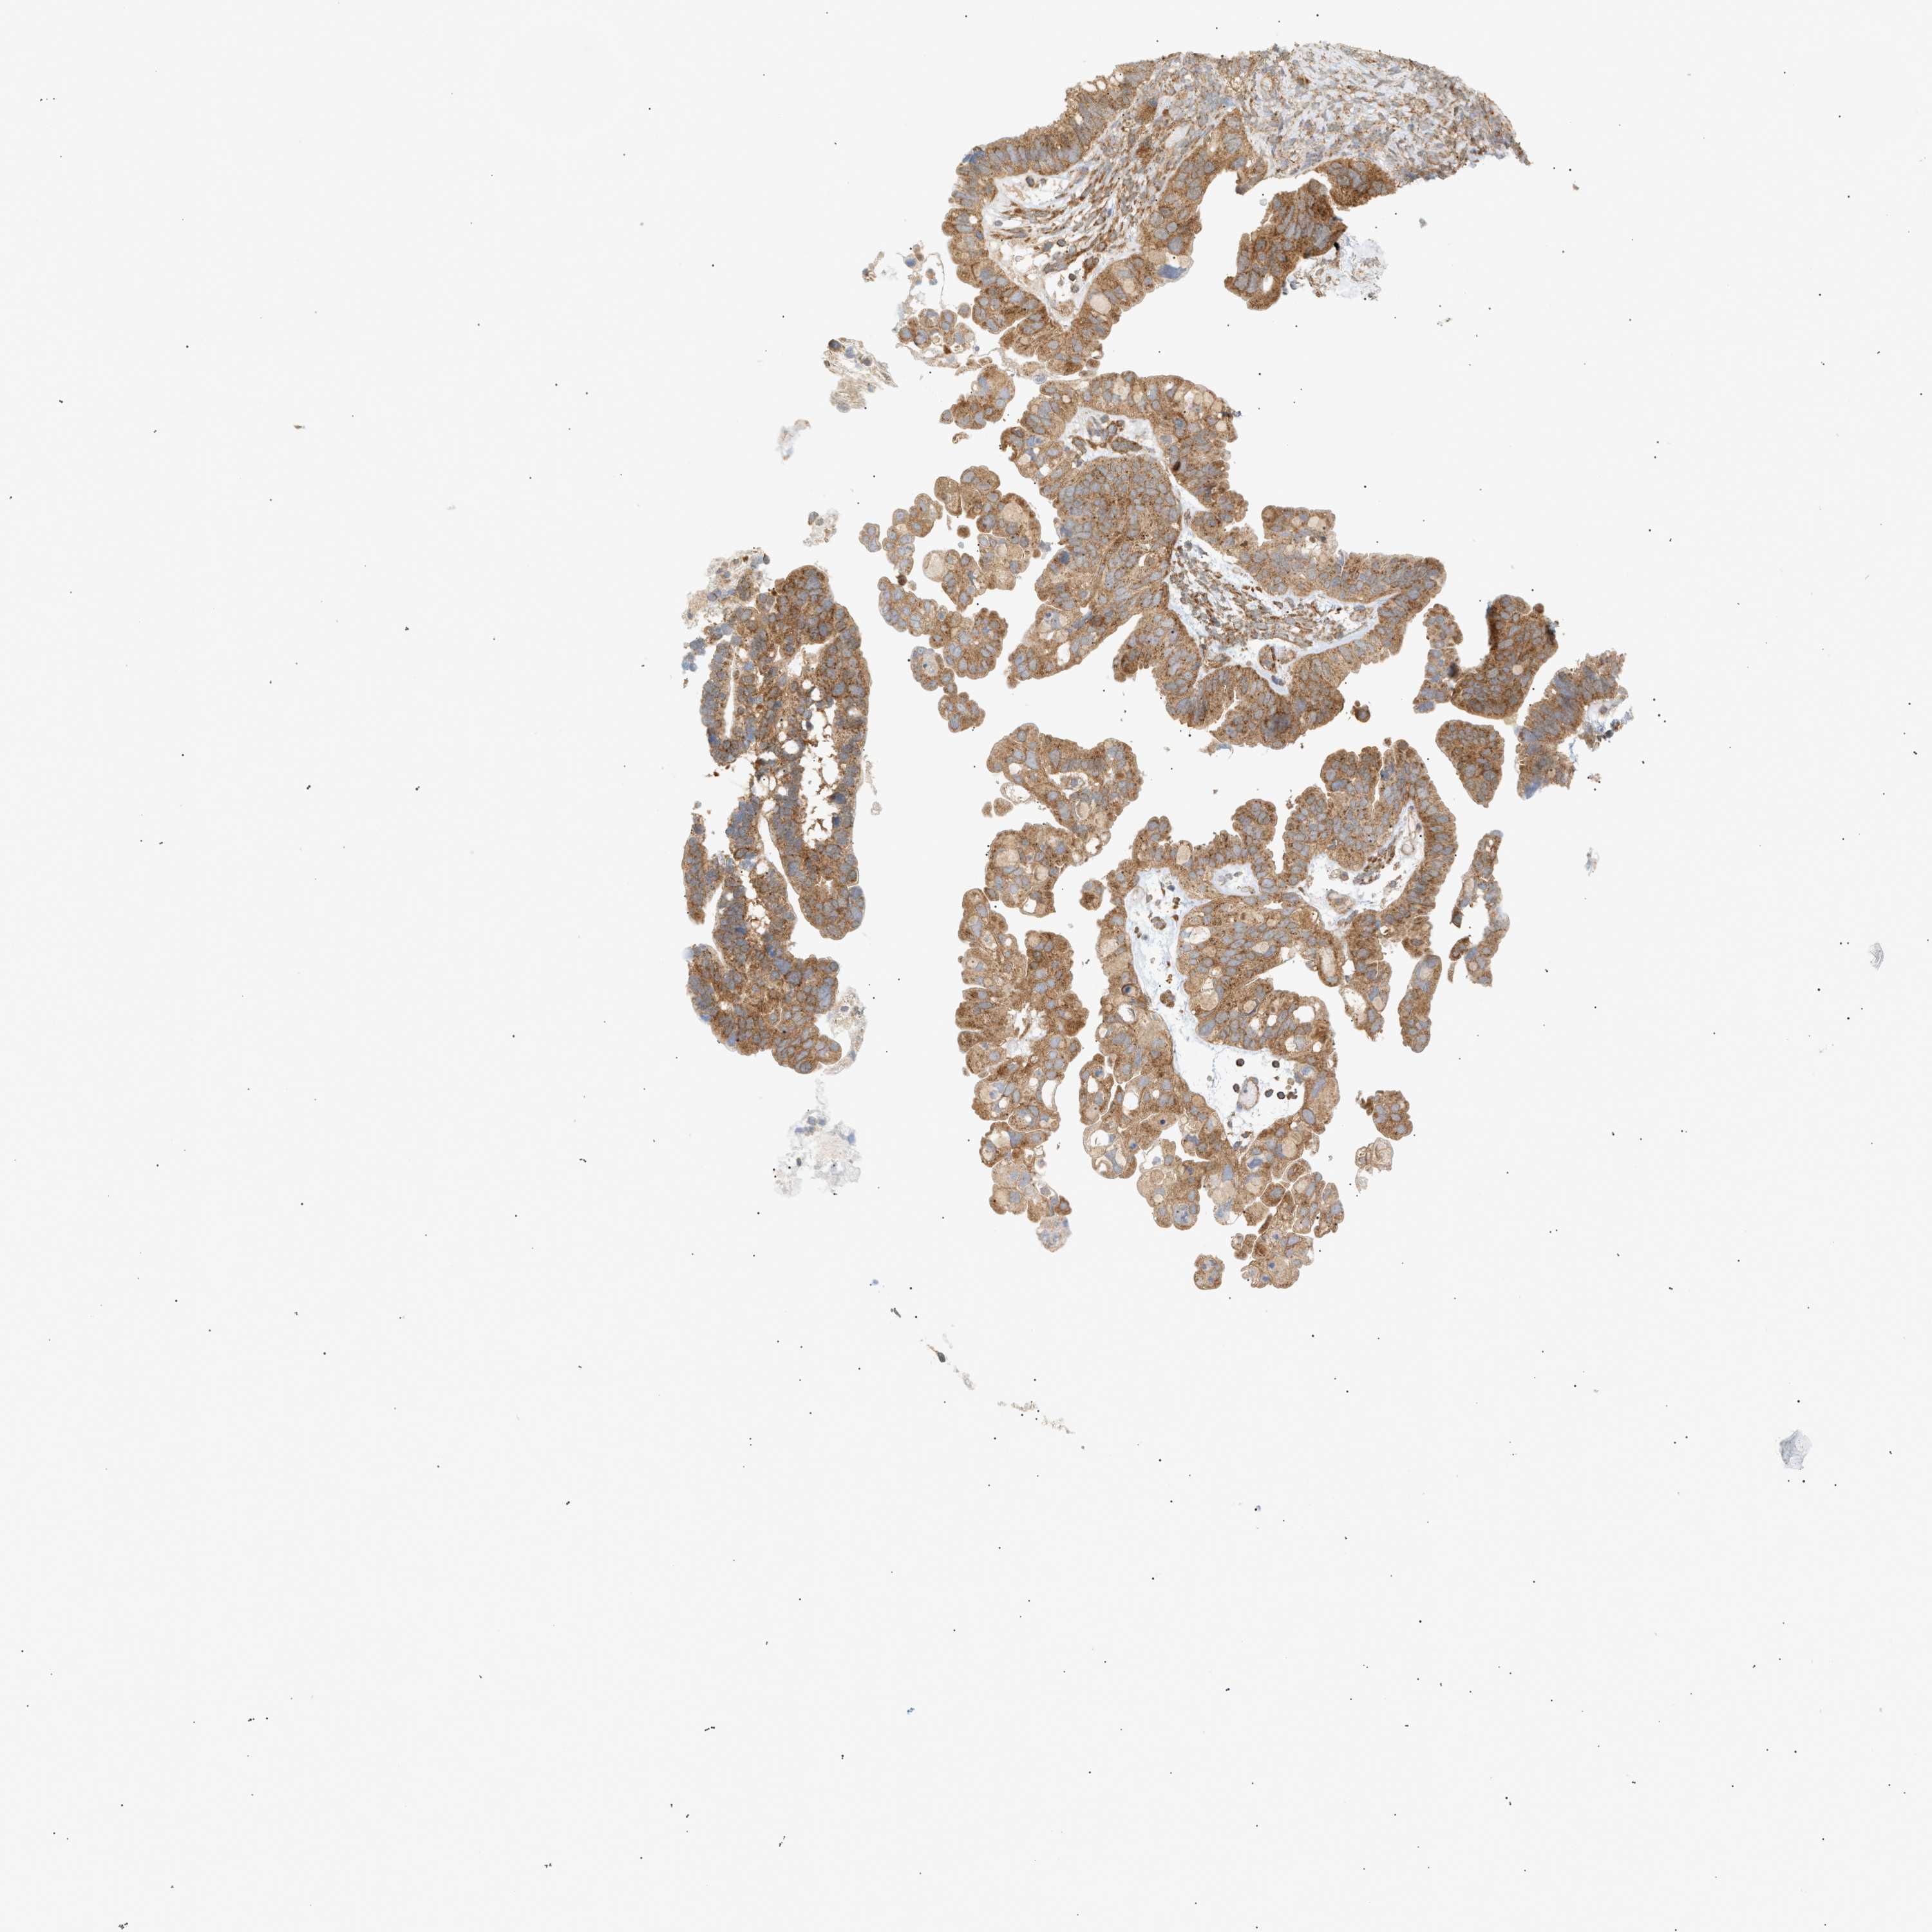

OVARIAN CANCER - Protein expressioni

A mouse-over function shows sample information and annotation data. Click on an image to view it in a full screen mode. Samples can be filtered based on level of antibody staining by selecting one or several of the following categories: high, medium, low and not detected. The assay and annotation is described here.

Note that samples used for immunohistochemistry by the Human Protein Atlas do not correspond to samples in the TCGA dataset.

Antibody stainingi

Antibody staining in the annotated cell types in the current human tissue is reported as not detected, low, medium, or high, based on conventional immunohistochemistry profiling in selected tissues. This score is based on the combination of the staining intensity and fraction of stained cells.

Each image is clickable and will lead to virtual microscopy that enables deeper exploration of all samples and also displays staining intensity scores, fraction scores and subcellular localization as well as patient and tissue information for each sample.

Antibody CAB005374

Cystadenocarcinoma, mucinous, NOS